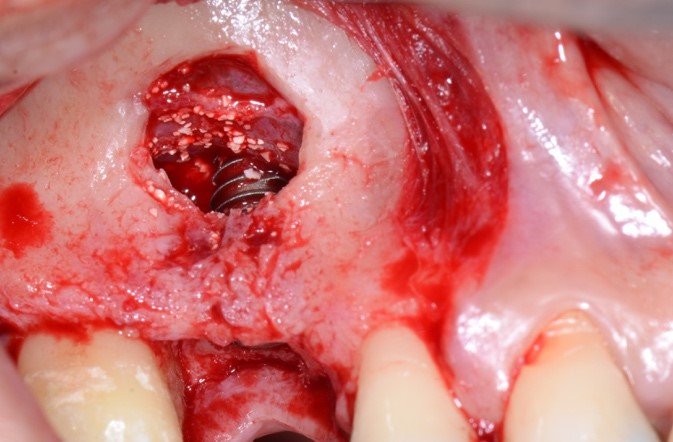

A irrigação da maxila é realizada por ramos de 2 principais vasos, a artéria alveolar superior posterior (AAPS) e a artéria infra-orbital (AIO), ramos da artéria maxilar 3,4. No estudo com tomografias de Khojastehpour et al 5 em 2016, eles encontraram anastomose na membrana entre as artérias AAPS e a AIO em 49.8% dos indivíduos, e do ponto de vista técnico nesssa condição, somente em casos de acidentes com rompimento da membrana sinusal poderia ocorrer hemorragias relevantes. Por outro lado, outros autores têm encontrado maior número de situações em que a AAPS se encontra intra-óssea, como nos estudos de Güncü et al 6 em 2011, e Ilgüi et al 7 em 2013, que observaram 68.2% e 71.1%, respectivamente. Quando a AAPS se encontra nessa última condição relatada, ocorre maior risco de dano vascular com hemorragia, especialmente se o canal vascular intra-ósseo for maior que 1 mm de espessura. Em média, alguns estudos têm demonstrado que a distância vertical do canal vascular da AAPS se apresenta próximo de 16 mm 5,7. Porém em casos de reabsorção do rebordo alveolar essa altura pode ser encontrada próximo de 11mm, segundo Rosano et al 4. A recomendação da tomografia como imagem de diagnóstico para identificação e mensuração da AAPS, pode estabelecer modificações estratégicas tanto na osteotomia, em relação ao desenho vertical e comprimento do implante, quanto na metodologia de instrumentação óssea. Podem ser usadas, por exemplo, ponteiras piezoelétricas sob irrigação para melhorar a visualização operatória e diminuir o risco de laceração vascular. As figuras de 1 a 12, demonstram caso clínico de técnica cirúrgica com osteotomia modificada, usando unidade piezo Mectron para remoção da parede lateral e preservar a AAPS, que foi diagnosticada em exame tomográfico durante a fase pré-operatória.

As figuras 16 e 17 mostram o transoperatório de um caso de hemorragia após dano a AAPS durante procedimento de osteotomia para rotação superior da janela óssea. A hemorragia durante a cirurgia trouxe dificuldades na visualização da membrana e a mobilização da janela para o interior da cavidade para formar o teto sobre a membrana sinusal. Somente após o preenchimento total com enxerto ósseo bovino particulado e cobertura com membrana hemostática de colágeno, houve diminuição do fluxo sanguíneo local. Mesmo com a manobra transoperatória, ocorreu a formação de extenso blefarohematoma periorbital e hematoma cérvico-facial. Segundo relato da paciente, o edema palpebral e na região parotídeo-masseterina provocaram dificuldade na abertura palpebral e bucal. As figuras 18 e 19 demonstram os hematomas já em regressão no 110 dia de pós-operatório (PO), já em uso de compressas mornas desde o 70 dia de PO, associado a moderada massagem local para drenagem hemo-linfática nos tecidos com pomada fibrinolítica.